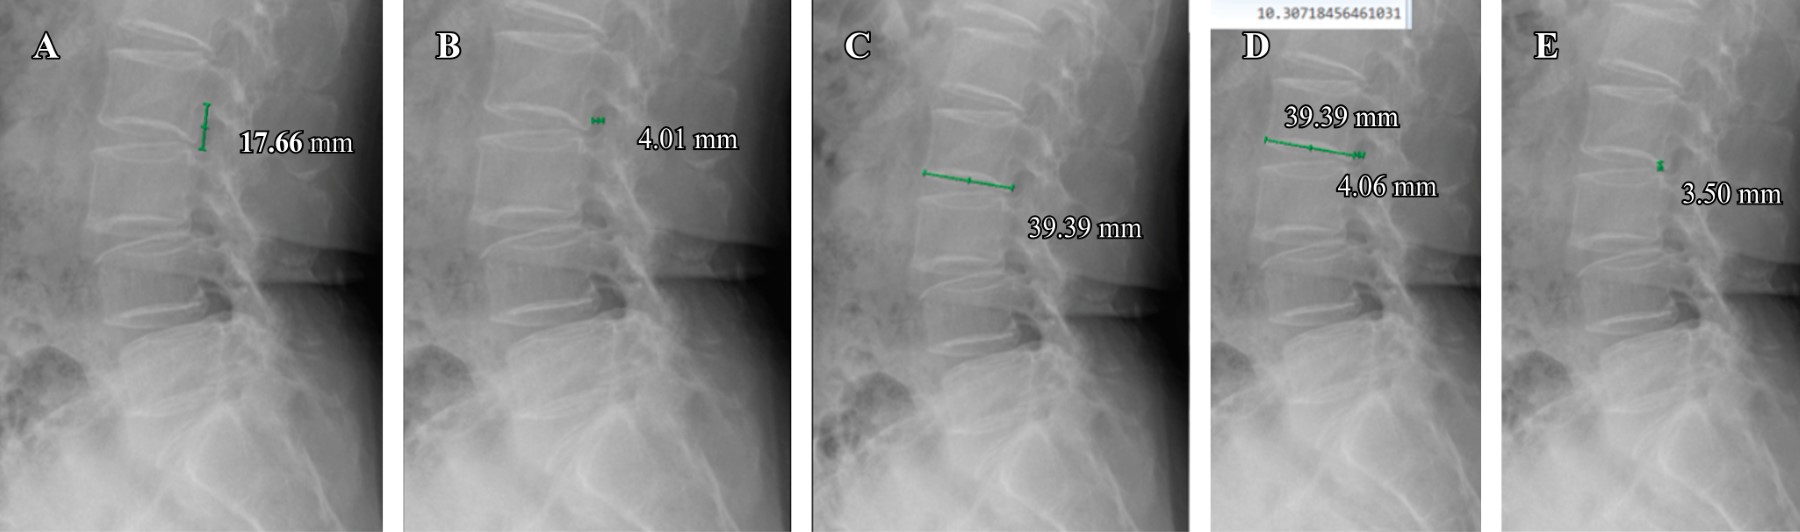

Introducción: la estenosis foraminal lumbar se define como el estrechamiento del canal lateral por donde sale la raíz nerviosa del canal espinal en la columna lumbar, ocurre de 8-11% en pacientes mayores de 40 años. El fallo en la detección y descompresión del foramen representa 60% de las causas de cirugía lumbar fallida. Este estudio tuvo como objetivo generar un índice que evalúa el grado de estrechez foraminal y así apoyar la toma de decisiones para una descompresión foraminal directa o indirecta. Material y métodos: se realizó un estudio transversal, donde se incluyeron 49 pacientes a los cuales se les midieron los cinco forámenes lumbares con rayos X y resonancia magnética simple. Estas mediciones incluyeron principalmente el ancho foraminal y la plataforma vertebral inferior del cuerpo vertebral superior y se correlacionaron para formar un índice ancho foraminal/plataforma vertebral inferior. Resultados: el índice ancho foraminal/plataforma vertebral inferior < 10% tiene un OR de 3.07 en la radiografía lateral, un OR de 3.59 en la radiografía en flexión y un OR de 4.01 en la radiografía en extensión. En la resonancia magnética se obtuvo un OR de 0.195 para los forámenes izquierdos y un OR de 3.07 para los forámenes derechos. Conclusión: este estudio abre el camino para una mayor exploración de los resultados clínicos preoperatorios y postoperatorios en diversos métodos de descompresión quirúrgica guiados por el índice FW/LE. Para mejorar la toma de decisiones, se recomienda realizar una investigación que compare los hallazgos clínicos preoperatorios y postoperatorios en pacientes individuales, teniendo en cuenta sus mediciones del índice FW/LE.

Figura 1